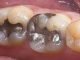

Affordable All-on-4 Dental Implants in Brisbane: Your Comprehensive Guide

Introduction: Are you considering All-on-4 dental implants but worried about the cost? Sandgate Bayside Dental is here to make this transformative procedure accessible to...